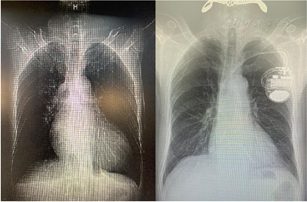

胸片:两肺纹理增多,心影增大,主动脉硬化。

术后患者长期服用阿司匹林100 mg/d,沙库巴曲缬沙坦100 mg/d,比索洛尔2.5 mg/d,螺内酯20 mg/d治疗,同时坚持低盐饮食(2~3 g/d),每日晨起监测体重,体重维持在68~70 kg。1个月后复查心超提示:左室壁收缩活动普遍减弱,左室收缩功能中度减退,LVEF:0.37.左房增大(42 mm)。6个月后复查心超:左室壁收缩活动普遍减弱,左室收缩功能中度减退,LVEF 0.40,左房增大(44 mm)。14个月后复查心超:左房增大(44 mm),LVEF 0.57(图5)。同时复查胸片:心影明显缩小(图6)。患者心衰症状明显好转。